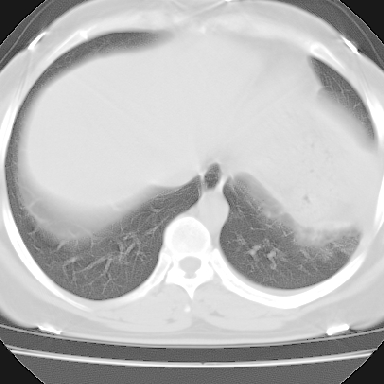

左下肺肿块影,内可以见小泡征,并见厚壁空洞形成,洞内缘凹凸不平,可见壁结节。靠近胸膜侧可见胸膜凹陷征。左侧胸腔内可见少量低密度积液影。右肺可见两处高致密的小结节影。

考虑:左下肺周围型肺癌伴右肺转移

左下肺肿块影,内可以见小泡征,并见厚壁空洞形成,洞内缘凹凸不平,可见壁结节。靠近胸膜侧可见胸膜凹陷征。左侧胸腔内可见少量低密度积液影。双肺可见多发性小结节影。

考虑:左下肺癌性空洞伴两肺转移

左下肺有空洞,壁厚薄不均,壁结节,两肺多发小结节影,腋窝下可疑淋巴结肿大,综上所述考虑周围性肺癌并两肺转移可能性大,建议穿刺活检。

右肺多发小结节影,边界清楚,符合转移瘤的特点;2、左下肺偏心性空洞影,右侧乳腺内高密度影,需要查体除外右侧乳腺肿瘤;3、腋窝淋巴结肿大,考虑转移。